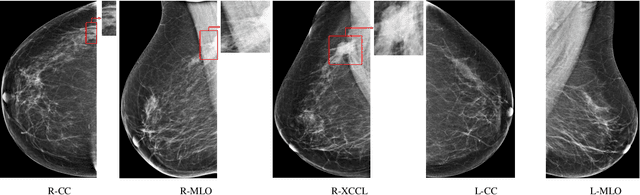

Abstract:Automatic methods for early detection of breast cancer on mammography can significantly decrease mortality. Broad uptake of those methods in hospitals is currently hindered because the methods have too many constraints. They assume annotations available for single images or even regions-of-interest (ROIs), and a fixed number of images per patient. Both assumptions do not hold in a general hospital setting. Relaxing those assumptions results in a weakly supervised learning setting, where labels are available per case, but not for individual images or ROIs. Not all images taken for a patient contain malignant regions and the malignant ROIs cover only a tiny part of an image, whereas most image regions represent benign tissue. In this work, we investigate a two-level multi-instance learning (MIL) approach for case-level breast cancer prediction on two public datasets (1.6k and 5k cases) and an in-house dataset of 21k cases. Observing that breast cancer is usually only present in one side, while images of both breasts are taken as a precaution, we propose a domain-specific MIL pooling variant. We show that two-level MIL can be applied in realistic clinical settings where only case labels, and a variable number of images per patient are available. Data in realistic settings scales with continuous patient intake, while manual annotation efforts do not. Hence, research should focus in particular on unsupervised ROI extraction, in order to improve breast cancer prediction for all patients.